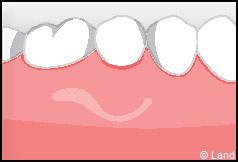

LES TECHNIQUES SANS APPORT DE GENCIVE :

Elles font appel à des lambeaux de gencive restante à proximité des récessions, qui sont déplacés et repositionnés sur la récession.

Dans ce cas le lambeau est déplacé latéralement pour combler la récession.